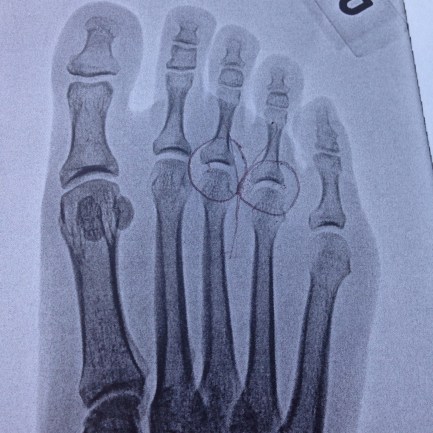

I am very happy to report it’s not broken and the quest towards the finish line continues. I have some inflamed metatarsals that needed some rest and extra padding. One medical professional I spoke with about it this week asked me about any trauma to the area and I said none that I could think of. Then he asked me how long my last long run was. When I said almost three hours, he laughed and reminded me that to most feet, that’s considered trauma.